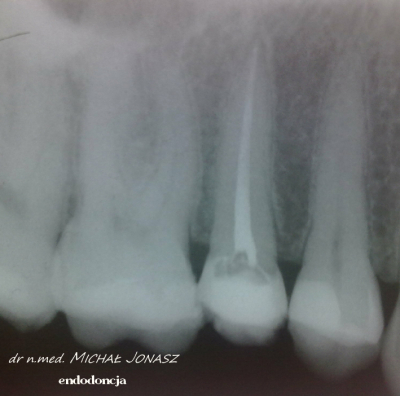

Zmiany okołowierzchołkowe to ogniska zniszczenia kości wokół wierzchołków korzeni zębów. Przewlekłe, nieleczone zmiany zapalne w obrębie korzeni zęba mogą powodować duże uszkodzenia kości i skutkować utratą zębów. Reendo polega na usunięciu materiału, którym wypełnione są kanały i zlokalizowaniu nieprawidłowości, czyli niedostatecznie oczyszczonego lub wypełnionego kanału albo pozostawionego, złamanego narzędzia w jego świetle. Dzięki mikroskopowi problemy anatomiczne, takie jak wąskie, zarośnięte kanały, zakrzywione korzenie, boczne, nietypowe odnogi są możliwe do wyeliminowania.

Diagnostyka obrazowa i wprawne oko Stomatologa są podstawą do podjęcia powtórnego leczenia kanałowego. Wychwycenie zmian patologicznych kierujących na powtórne leczenie kanałowe często jest efektem wnikliwej analizy zdjęć RTG. Powtórnego leczenia kanałowego wymagają zęby, których kanały korzeniowe nie zostały prawidłowo wypełnione. Im dłuższy czas upływa od zakończenia pierwotnego leczenia kanałowego, tym mniejsza szansa, że ząb da o sobie ponownie znać. Nieprawidłowo przeleczony kanałowo ząb, to potencjalnie ogromne ryzyko dla pacjenta. Ząb źle leczony kanałowo przypomina o sobie po wielu latach, bądź w postaci dolegliwości bólowych, bądź przez wolno, bezobjawowo rozwijającą się torbiel. Wytworzenie się torbieli wymaga już interwencji z zakresu chirurgii stomatologicznej. W takiej sytuacji po leczeniu powtórnym pacjent jest kierowany do chirurga na zabieg wyłuszczenia torbieli.

Na zdjęciu RTG efekt leczenia endodontycznego można ocenić po 3 – 6 miesiącach. Każde kanałowe leczenie należy systematycznie kontrolować poprzez wykonywanie rutynowych zdjęć radiologicznych, tak by zawczasu uniknąć nieprzyjemnych problemów.